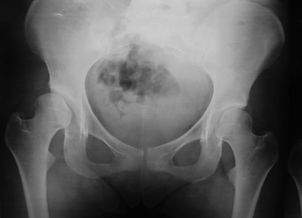

Pinzamiento Femoroacetabular

Displasia del desarrollo de la cadera